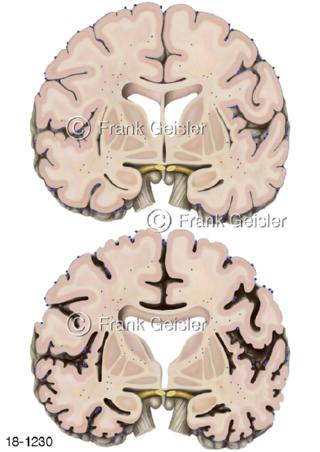

18-1230 Hirnschnitt Alzheimer-Krankheit Demenz

18-1231 Frontalschnitt gesundes Gehirn und Alzheimer-Krankheit Morbus Alzheimer Demenz